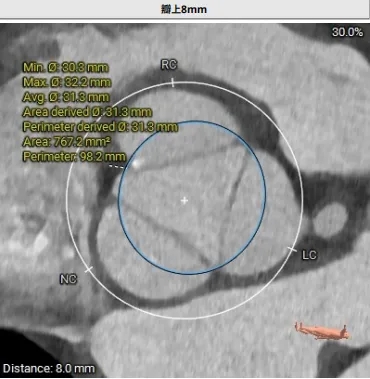

瓣上结构测量

周长77.3 周长径24.6

周长82.8 周长径26.4

周长92.8 周长径29.5

周长98.2 周长径31.3